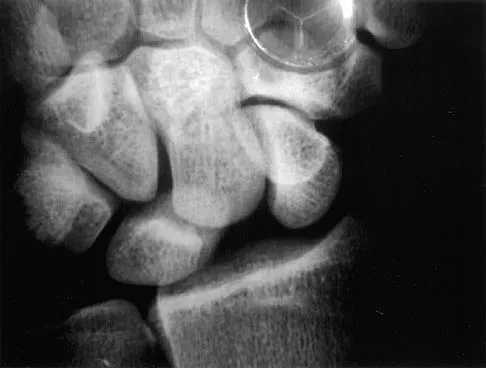

The condition shown in Figures 9a and 9b is most likely the result of

Explanation

The clinical photograph and radiograph show gout, which is the result of urate deposition in the joint and soft tissues. Radiographs frequently reveal periarticular erosions. The crystals are intracellular and negatively birefringent under the polarized microscope. Treatment for acute flares include colchicines, indomethacin, and corticosteroids (including injections). Medications such as allopurinol help prevent recurrent flares. Tophi such as that seen in this patient are often confused with and associated with infection. Wortmann RL, Kelley WM: Crystal-induced inflammation: Gout and hyperuricemia, in Harris ED, Budd RC, Firestein GS, et al (eds): Kelley's Textbook of Rheumatology, ed 7. New York, NY, Elsevier Science, 2005, pp 1402-1429. Trumble TE (ed): Hand Surgery Update 3: Hand, Elbow, & Shoulder. Rosemont, IL, American Society for Surgery of the Hand, 2003, pp 433-457.